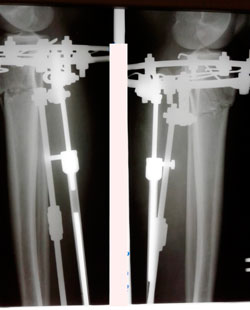

Рентген в 90дней.

IMG_1444-25-02-19-05-32.JPG

IMG_1443-25-02-19-05-32.JPG